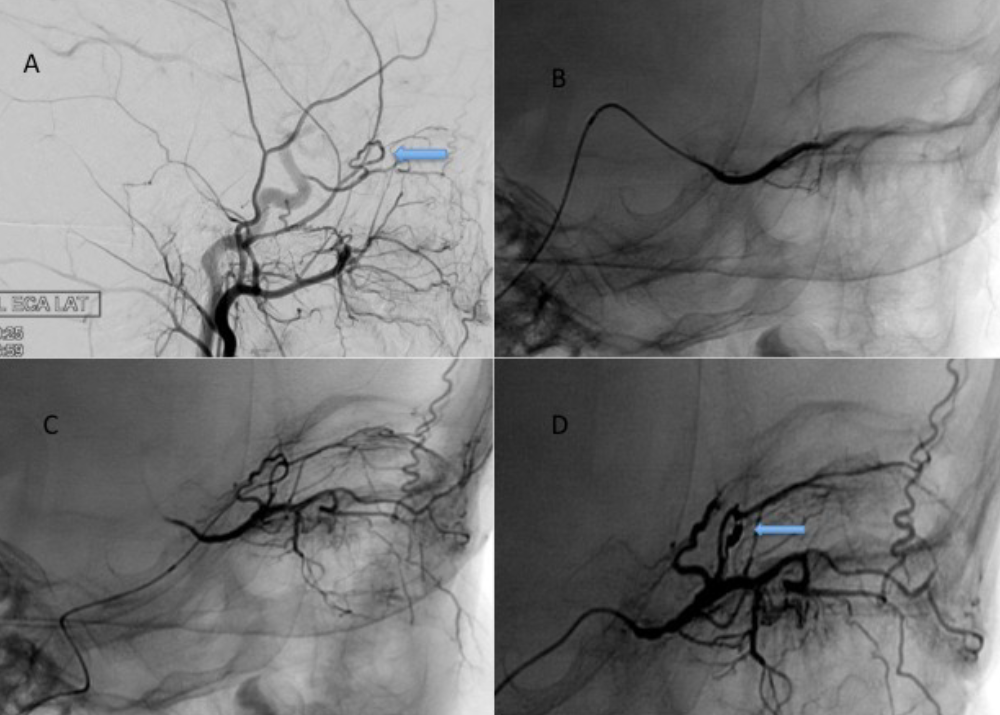

Figure 2. An example of meningo-ophthalmic collateral. After the contrast medium injection of the left external carotid artery, (A) the meningo-ophthalmic collateral (arrow sign) between the middle meningeal artery and the ophthalmic artery is observed. OA shows an inverse filling due to the meningo- ophthalmic collateral. (D) After the coil embolization of the meningo-ophthalmic collateral (arrow sign), it is seen that the OA is normally filled anterogradely after the superselective catheterization of the OA

Figure 3. DSA images of a 50-year-old woman who underwent preoperative tumor embolization due to left parafalcine meningioma. In ECA injections (A) and (B), posteroanterior images show anastomosis between the sphenoidal branch of the middle meningeal artery and the lacrimal artery (arrow sign)